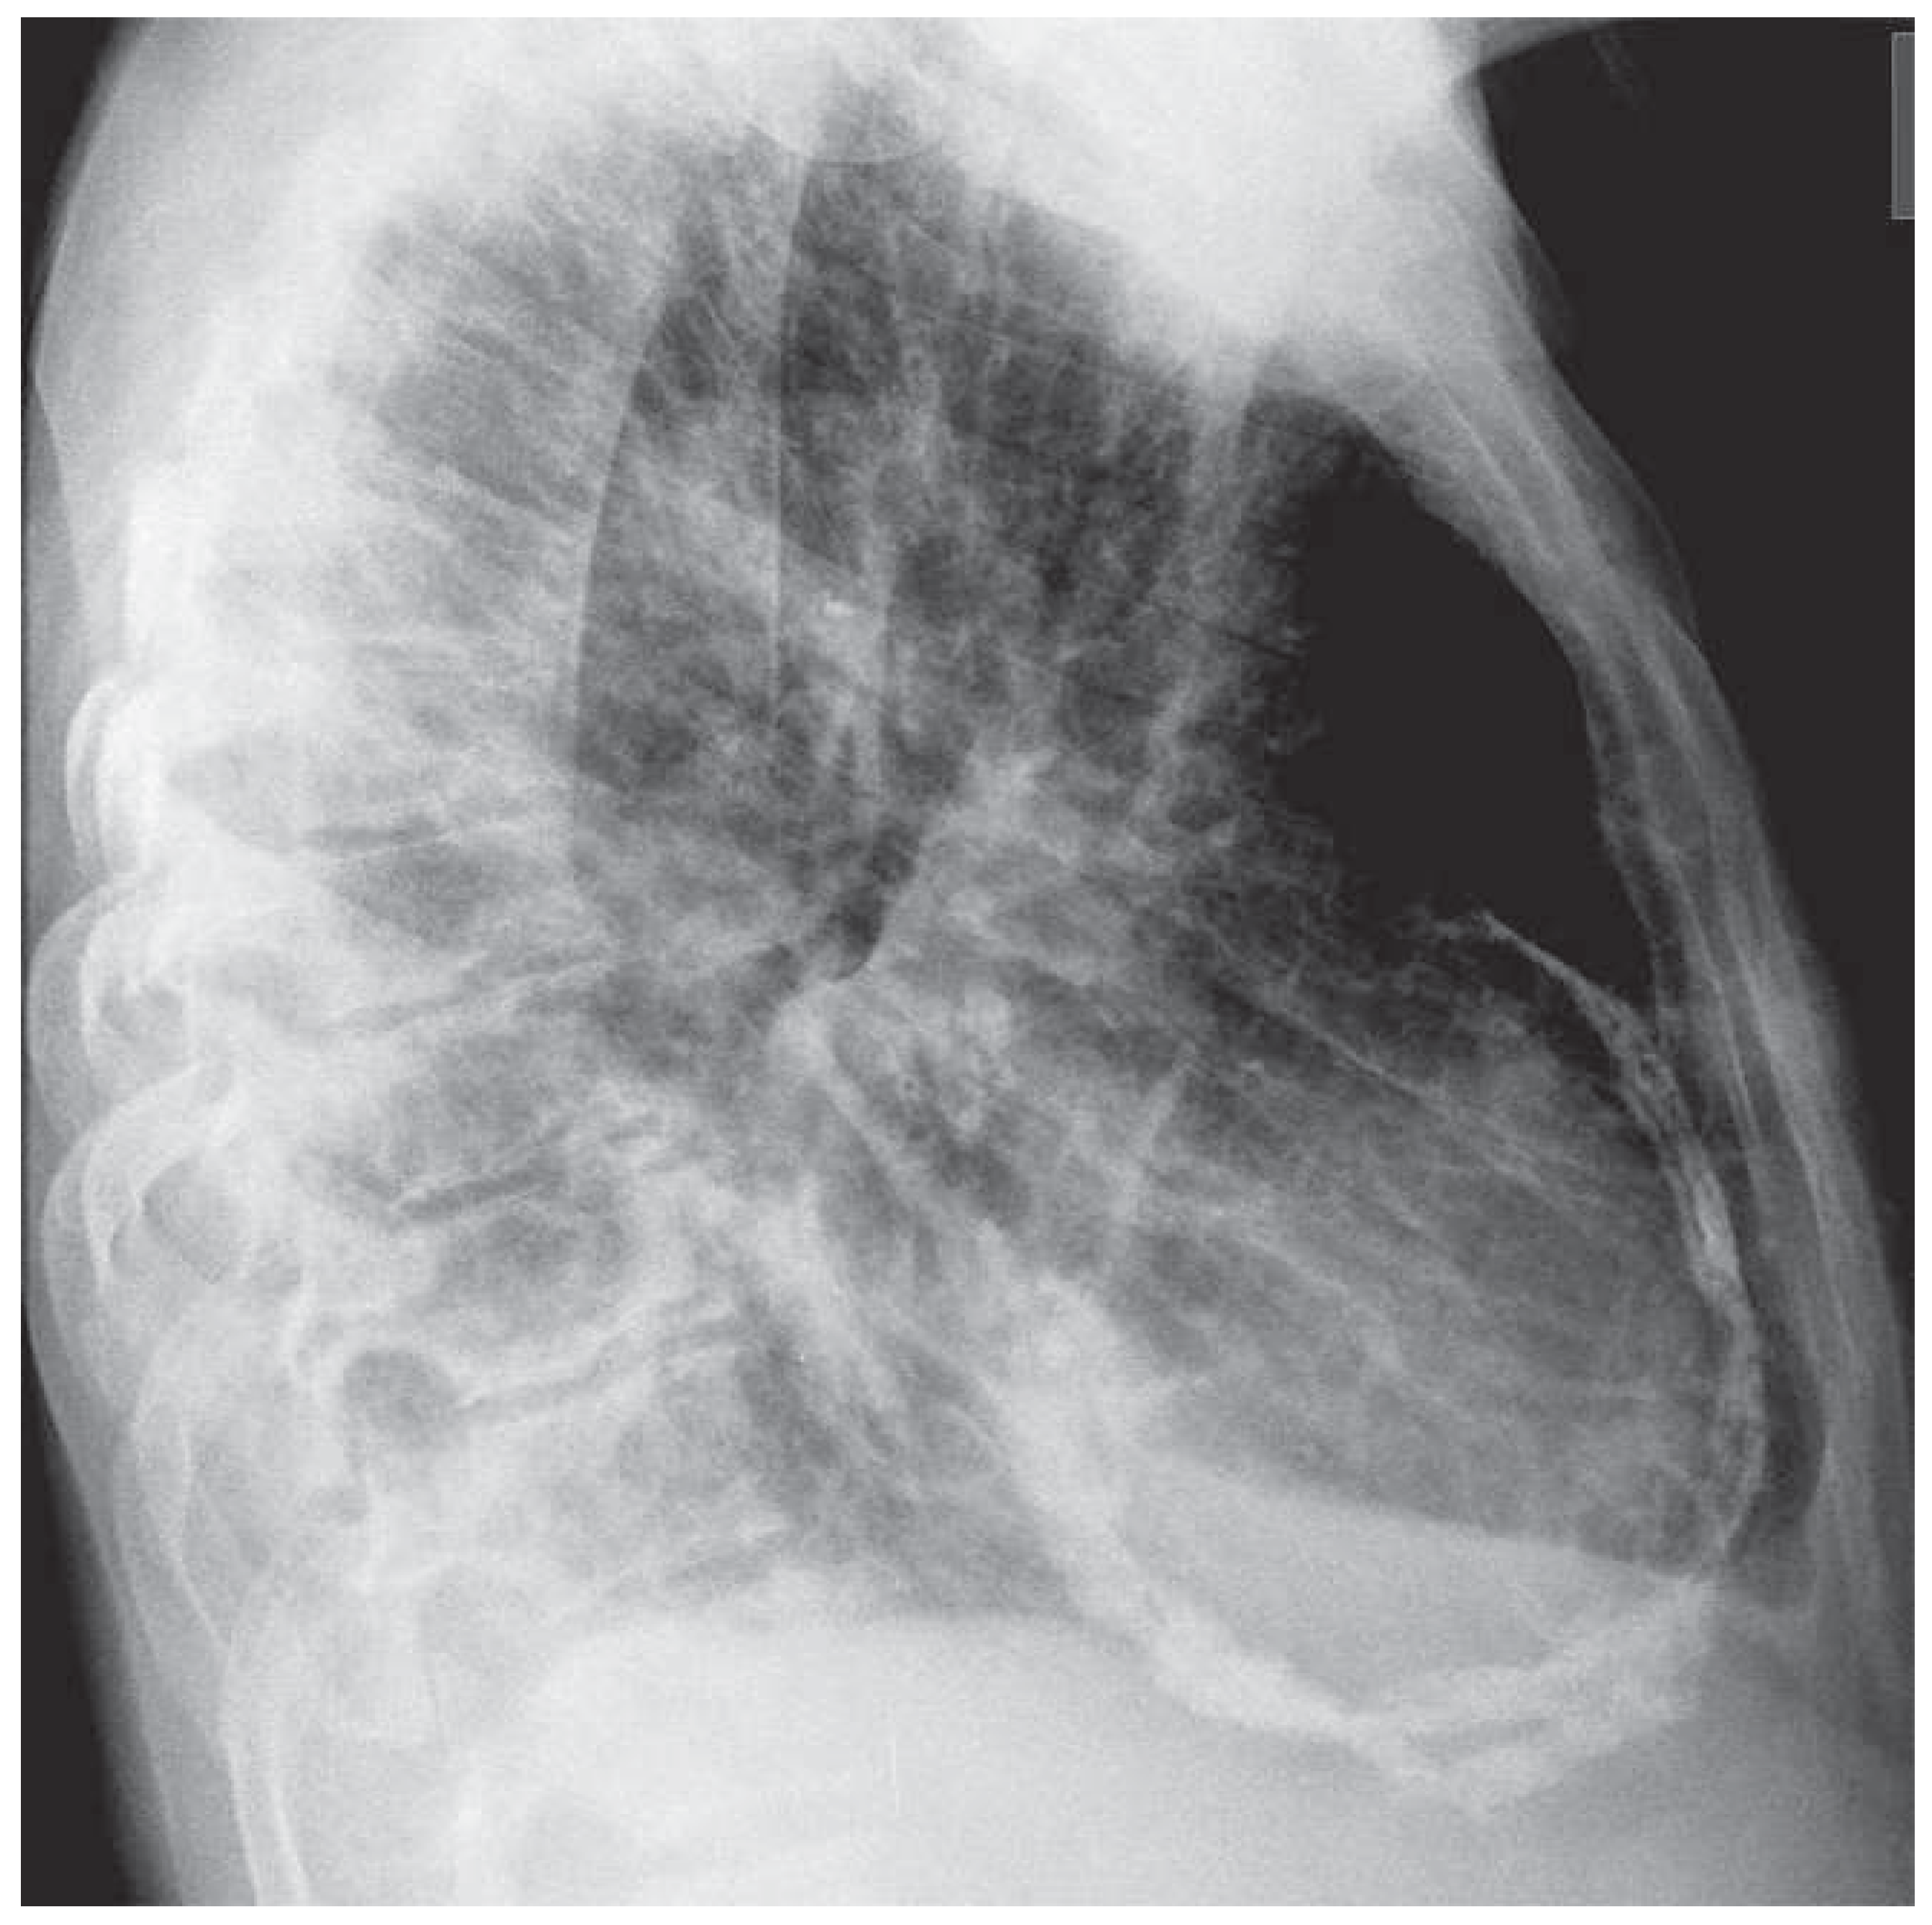

A 56-year-old man was admitted with massive signs of right heart failure, which had evolved over weeks. Chest X-ray revealed extensive pericardial calcifications in the lateral view ( Figure 1). Transthoracic echocardiography showed only mildly impaired biventricular systolic function but a dilated inferior vena cava without respiratory variability. The peak early mitral annular velocities (e’) assessed by pulsed wave tissue Doppler at the septal and lateral mitral annulus were 8 and 6 cm/s, and the ratio of the peak early transmitral velocity (E) to e’ (E/e’), based on an average e’ of 7 cm/s, was only 10 (Figure 2A,B,D). The pulmonary venous flow was clearly abnormal however (Figure 2C). There was an exaggerated respiratory variability of mitral in-flow (Figure 3).

Figure 1. Chest X-ray (lateral view) showing extensive pericardial calcifications.